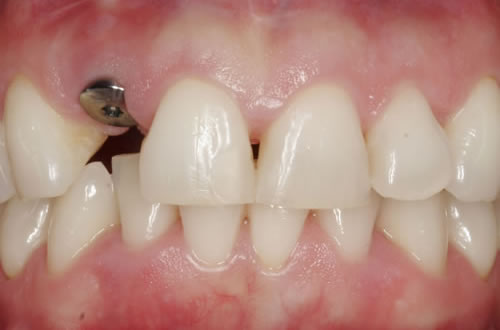

Diese Beispiele ließen sich endlos fortführen. Sie zeigen die Probleme bei der Versorgung zahnloser Kiefer, wie sie immer wieder geschildert werden. Mit Hilfe sehr einfacher Maßnahmen kann durch die Einpflanzung künstlicher Zahnwurzeln eine instabile Prothese soweit befestigt werden, dass die Kau- und Sprechfunktion wieder hergestellt ist. Manchmal kann die alte Prothese weiterverwendet werden, in dem man in die Prothesenbasis Sekundärteile einarbeitet, die für Halt sorgen (Abb. 3.5, 3.6). Bei aufwendigeren Steg- oder Teleskoparbeiten muss auch der Zahnersatz der auf den Implantaten fixiert wird neu angefertigt werden. Diese Arbeiten werden dann brückenartig und sehr grazil gestaltet. (Abb. 3.7 bis 3.12).

Abb. 3.7: Individuelle Stegversorgung aus Stahl auf vier Implantaten im zahnlosen Unterkiefer.

Abb. 3.8: Individuelle Stegversorgung aus Gold auf vier Implantaten im zahnlosen Unterkiefer.

Abb. 3.9: Prothesenansicht von unten mit grazil eingearbeiteten Halteelementen.

In bestimmten Situationen kann auch die Versorgung durch einen festsitzenden Zahnersatz, also durch eine Brücke, sinnvoll sein (Abb. 3.13, 3.14). Hier müssen allerdings relativ viele Pfeiler eingepflanzt werden. Mit der Anfertigung einer Brücke entstehen gewisse Probleme bei der notwendigen Mundhygiene und natürlich sehr hohe Kosten. Daher wird sie nur in besonderen Fällen in Frage kommen.

Abb. 3.13: Zahnloser Unterkiefer mit 8 Implantaten festsitzend versorgt.

Abb. 3.14: Ansicht der einzementierten Brücke.